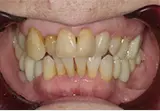

| 年齢/性別 | 70代女性 |

| 主訴 | 左下奥歯に痛みがある、全体的に治したい |

| 治療内容 | 全体的に歯周病やむし歯、根の治療を行い、仮歯を使用して咬合治療を実施。左上、右下、左下の計3本を抜歯し、右上には2本のインプラントを埋入しました。 |

| 治療期間 | 4か月(インプラントのみ) |

| 費用 | 1,116,500円税込 |

| リスク・副作用 | 炎症反応によって術後に腫れや副鼻腔炎が生じることがあります。その程度は、手術の範囲や方法によって異なりますが、多くの場合、時間の経過とともに徐々に治まります。 |